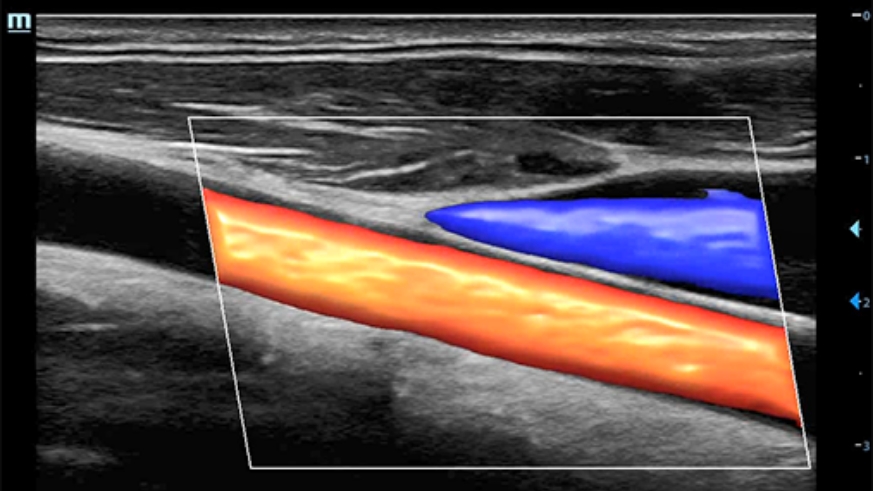

Echo Boost yang canggih

Terobosan beruntun Mindray untuk visualisasi gambar ultrasound terbaik.